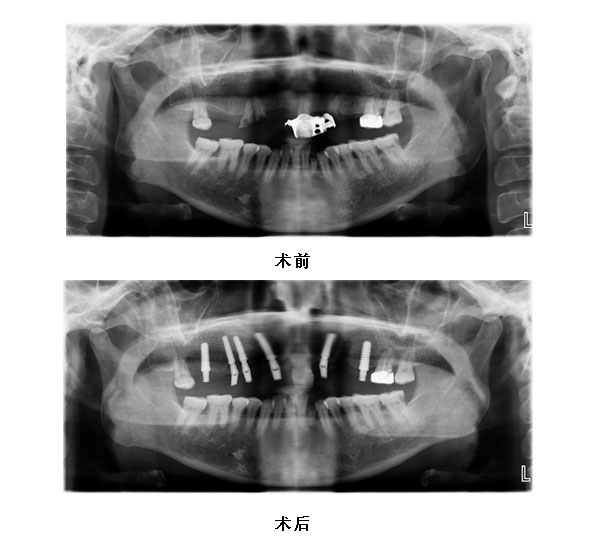

11 13 14 16 22 25种植修复 16至25烤瓷桥修